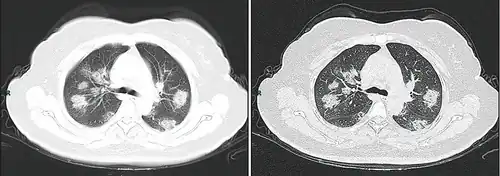

Dégâts pulmonaires

Les études en microscopie électronique et sur coupes histologiques de tissus pulmonaires (faites après autopsies) ont montré que les virions sont dans le poumon essentiellement localisés dans les pneumocytes[204].

Comme dans le cas du SARS, puis du MERS, la Covid se traduit dans l'arbre respiratoire par des lésions alvéolaires diffuses, caractérisées par des phases exsudatives et prolifératives de ces lésions, avec une congestion des vaisseaux capillaires et une nécrose systématique des pneumocytes, et très souvent une atteinte des membranes hyalines, un œdème interstitiel et intra-alvéolaire.

Les autopsies ont aussi révélé de fréquents événements thromboemboliques (« parfois cliniquement insoupçonnés au décès »)[205]. Outre une hyperplasie pneumocytaire de type 2, on a souvent observé une métaplasie squameuse avec atypie et micro-thrombus plaquettaire-fibrine[204],[206],[207],[208],[209].

L'infiltrat inflammatoire est toujours majoritairement composé de macrophages, souvent présents dans la lumière alvéolaire, souvent accompagnés de lymphocytes dans l'interstitium[204]. Des membranes hyalines se forment fréquemment, et une hyperplasie atypique des pneumocytes est également fréquemment constatée post-mortem. Le thrombus plaquettaire-fibrine des petits vaisseaux artériels peut être relié à une coagulopathie apparemment fréquente chez les malades de Covid-19 et qui selon Carsana & al (2020) devrait être l'une des principales cibles du traitement[204].